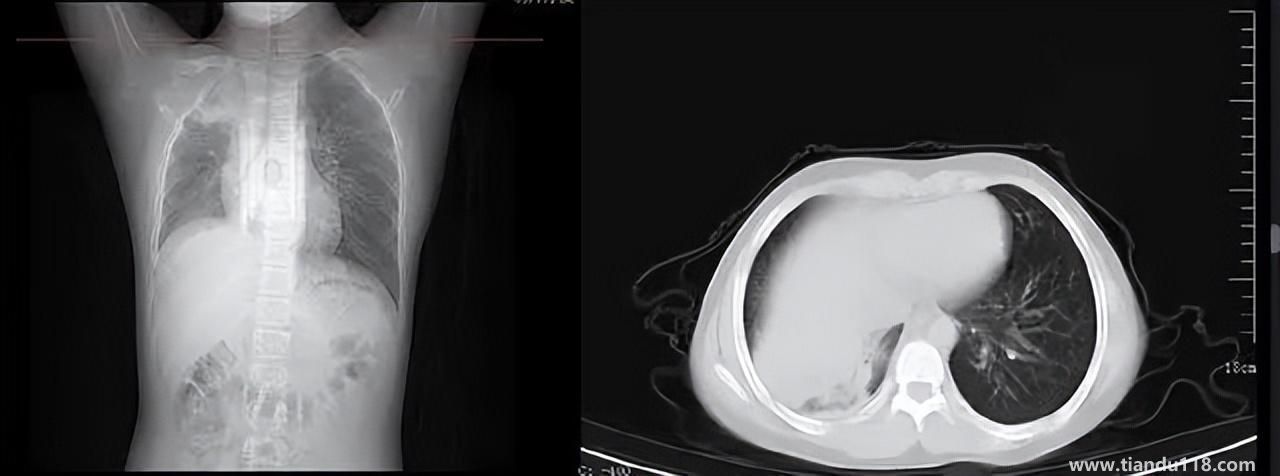

男孩咳嗽發(fā)熱在家硬扛成白肺(醫(yī)生表示以下幾種情況別硬“扛”) 男孩咳嗽發(fā)熱在家硬扛成白肺(醫(yī)生表示以下幾種情況別硬“扛”) 近日,一名12歲男孩咳嗽一周不就醫(yī),一側(cè)肺部“扛”成了“白肺”?!氨е鴥e幸心理一直在家硬‘扛’,沒(méi)想到‘扛’出這么重的??!”孩子家長(zhǎng)悔不... 小編 2022-12-28 939

感染新冠會(huì)變白肺?醫(yī)生:有年輕病例 感染新冠會(huì)變白肺?醫(yī)生:有年輕病例感染新冠會(huì)變白肺嗎?對(duì)此,有專(zhuān)家表示,造成“白肺”情況有很多種,感染新冠只是一種可能。少量患者肺有滲液 ,咳嗽不會(huì)引發(fā)白肺,有年輕人病例。... 小編 2022-12-27 608

3個(gè)辦法可提前預(yù)警白肺(咋預(yù)防“白肺”) 3個(gè)辦法可提前預(yù)警白肺(咋預(yù)防“白肺”)家里有老人,擔(dān)心出現(xiàn)“大白肺”、“沉默型缺氧”等情況,具體如何應(yīng)對(duì),提前預(yù)警?近日,大象新聞接到諸多咨詢(xún)。針對(duì)這些問(wèn)題,大象新聞?dòng)浾咦隽硕喾讲稍L。什么是白肺?對(duì)... 小編 2022-12-28 693

白肺與原始毒株和疫苗接種沒(méi)關(guān)系(國(guó)家衛(wèi)健委表示) 白肺與原始毒株和疫苗接種沒(méi)關(guān)系(國(guó)家衛(wèi)健委表示)從近期的公眾反映情況看,有的新冠病毒感染者在就診過(guò)程中發(fā)現(xiàn)了肺炎或者是CT出現(xiàn)了白肺的現(xiàn)象,有網(wǎng)友認(rèn)為,出現(xiàn)這種情況可能是跟感染了原始毒株或者接種疫苗有... 小編 2022-12-28 530

為何有人出現(xiàn)“白肺”?專(zhuān)家回應(yīng)和疫苗接種無(wú)關(guān) 為何有人出現(xiàn)“白肺”?專(zhuān)家回應(yīng)和疫苗接種無(wú)關(guān)國(guó)務(wù)院聯(lián)防聯(lián)控機(jī)制12月27日召開(kāi)新聞發(fā)布會(huì),針對(duì)有媒體提問(wèn)稱(chēng),從近期公眾的反映情況看,有的新冠病毒感染者在就診過(guò)程中發(fā)現(xiàn)了肺炎或者是CT出現(xiàn)了“白肺”的現(xiàn)... 小編 2022-12-27 817